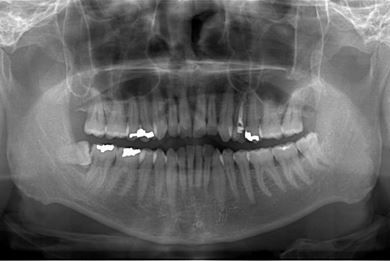

セラミック治療+歯肉歯槽骨整形術

| 性別/年齢 | 男性 / 45歳 | ||||||||||||||||||||||||||||||||

| 主訴 | 詰め物をしている歯が割れてしまったので、治療して欲しい。 | ||||||||||||||||||||||||||||||||

| 治療方針 | セラミック治療にて、審美的回復を行う。 | ||||||||||||||||||||||||||||||||

| 治療内容 | メタルボンドセラミッククラウン1本(メタルボンドセラミック用土台1本)、歯肉歯槽骨整形手術 | ||||||||||||||||||||||||||||||||

| 総治療費 | 157,185円 | ||||||||||||||||||||||||||||||||

| 治療期間 | 7ヶ月 |